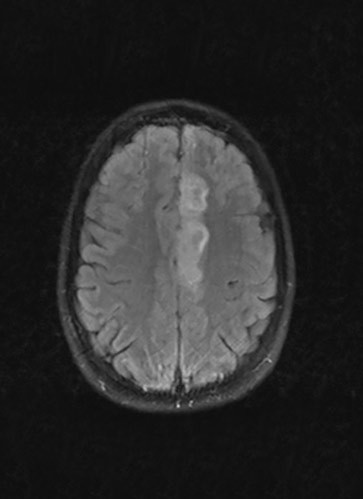

Cerebral MRI the day after admission (pictured left) revealed infarction of the left medial frontal lobe, corresponding to the area supplied by the left anterior cerebral artery, and time-of-flight MR angiography showed thrombosis in the A2 segment of the artery. The patient underwent extensive investigation, but the underlying cause of the infarct could not be determined. After two weeks, conventional cerebral angiography revealed a dissection in the A2 segment of the left anterior cerebral artery (pictured right). A month later she was back in full-time employment, and her NIHSS (National Institute of Health Stroke Scale) and modified Rankin Scale (mRS) scores were both 0.